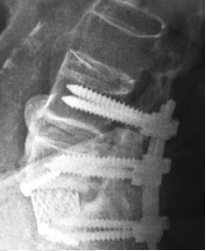

Mr O, an elderly man, was recently admitted for severe low back pain of two months duration. He had chronic low back pain on and off for many years. His pain this time was so severe that he could sit for only a short while. He could barely walk a few meters. The neurological examination was normal. X-ray of his lumbar spine revealed the feature of “’ bamboo spine’ typical of ankylosing spondylosis. There was a fracture through the ossified L5-S1 disc space which was widely opened. Flexion and extension x-ray showed there was considerable instability at the L5-S1 segment. Mr O underwent a two-stage surgery. The 1st stage was posterior L4 to S1 pedicle screw instrumentation. The 2nd stage anterior L5-S1 strut grafting with titanium mesh and fibular allografts was performed 5 days later. Post surgery, Mr O was relieved of his pain and was ambulating.

If a spinal fracture occurs, the bone displacement at the fracture site tends to be severe as all spine motions are concentrated at the fracture site. The excessive motion at the fracture site results in poor fracture healing. Hence the fracture in an ankylosed spine has to be treated with very rigid surgical stabilization. This usually involves two stages anterior and posterior stabilization.